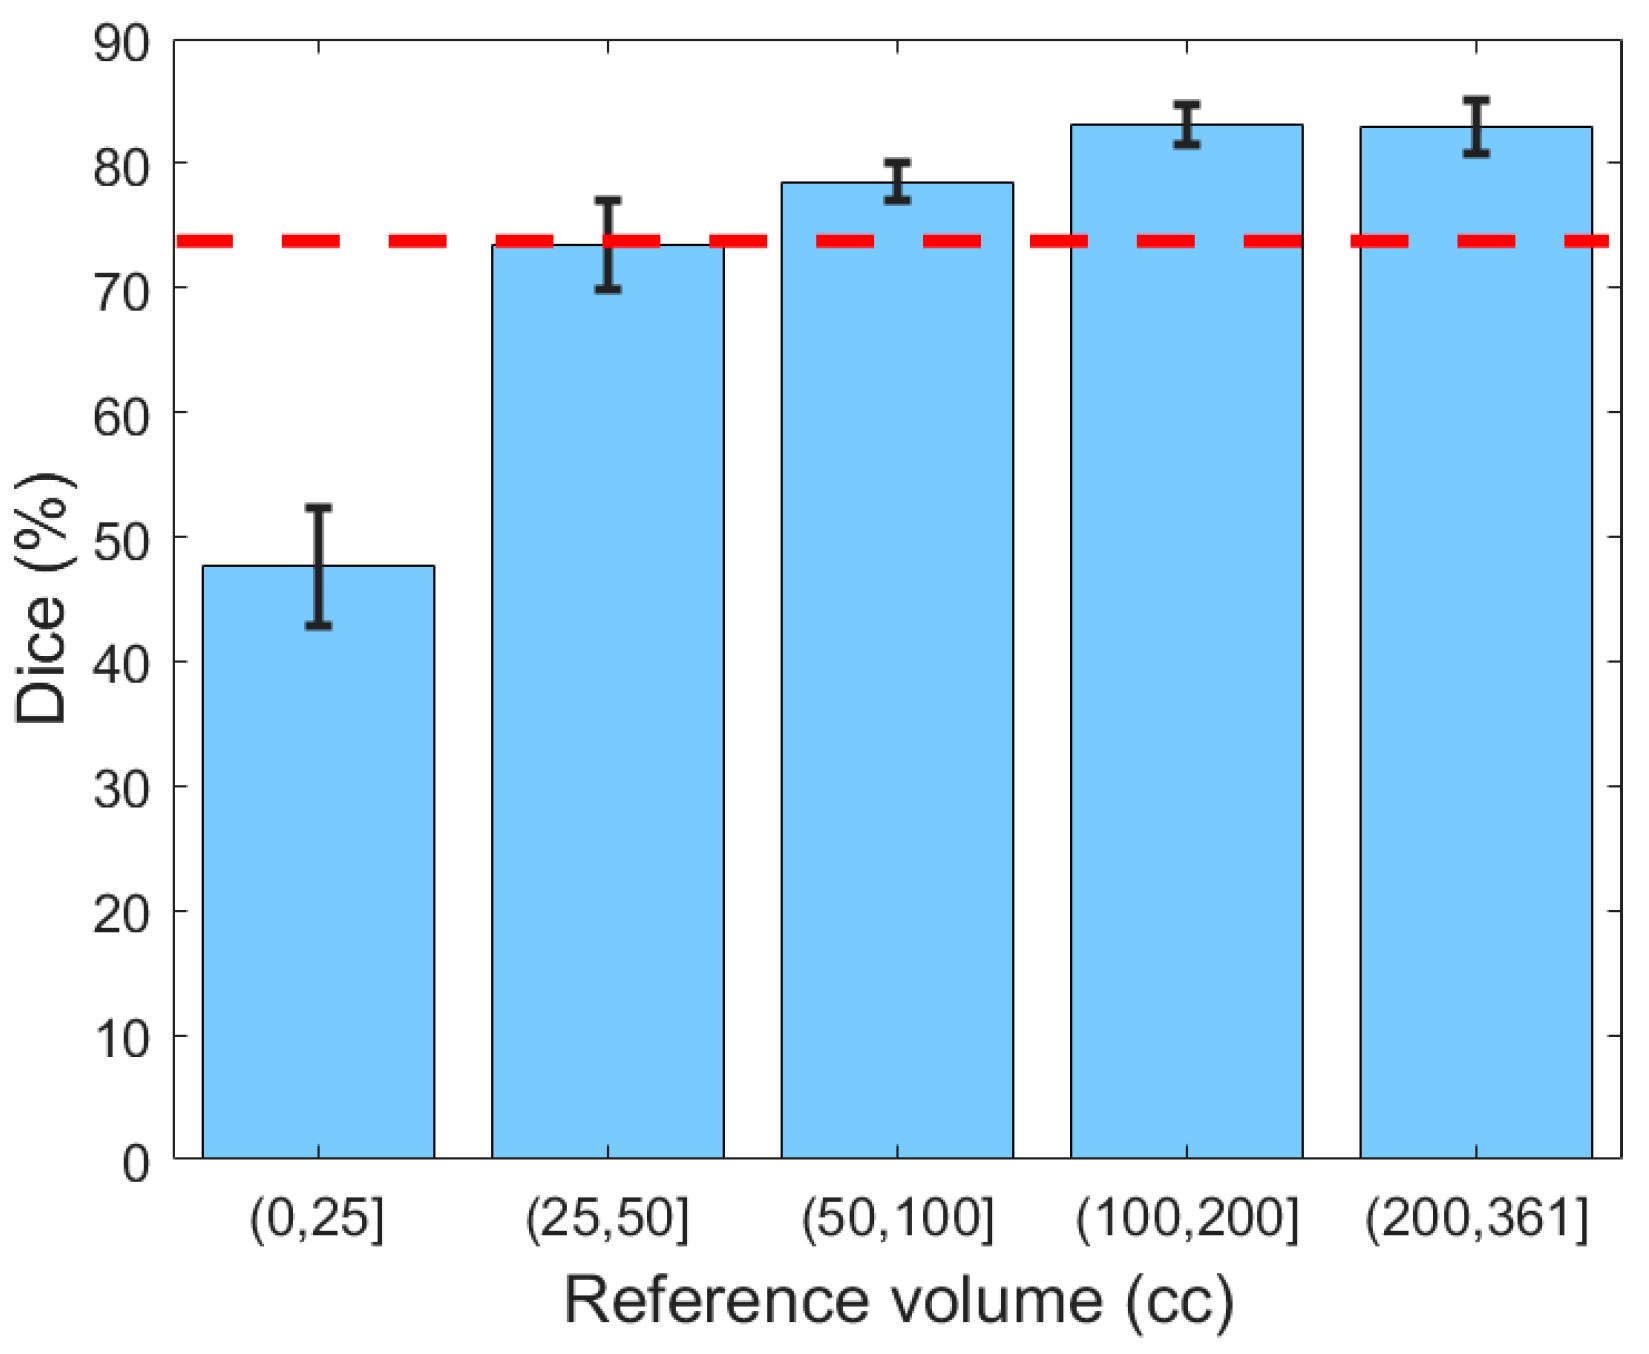

Next, the generalizability of the proposed segmentation approach was further validated by analyzing segmentation performance with respect to different ranges of hematoma volume (

Figure 8). The reference volume was calculated using the ground truth and was discretized by thresholding at 25, 50, 100, and 200 cc. It can be concluded from

Figure 8 that Dice values for subjects with mild SDH (47.67%) were lower than for those with more severe SDH (79.97%), possibly because the smaller regions were less represented in the classifier. Moreover, for small lesions, even a small deviation in segmentation has a large impact on the Dice similarity value.

Figure 8.

The Dice similarity coefficient based on the severity of hematoma. Error bars represent ±1 standard errors, the 68% confidence interval. The red dashed line indicates the human benchmark.

Figure 8.

The Dice similarity coefficient based on the severity of hematoma. Error bars represent ±1 standard errors, the 68% confidence interval. The red dashed line indicates the human benchmark.